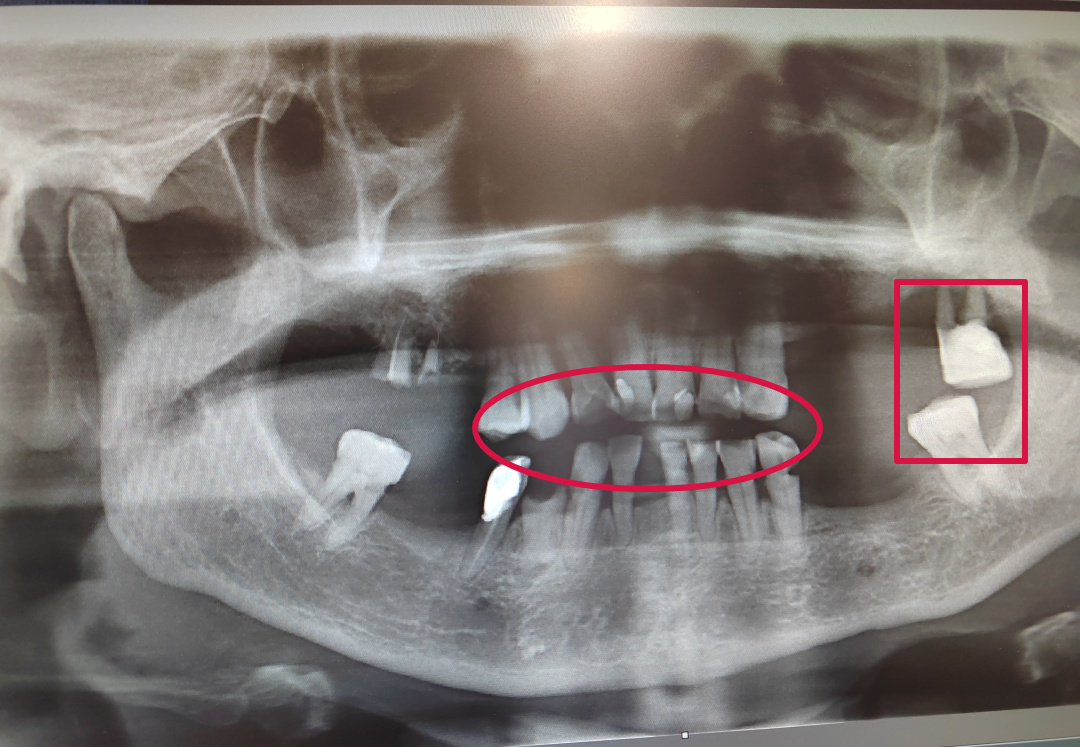

具体情况如下图所示▽

邢主任看着影像检查片向张阿姨细细解说着她目前的情况并给出了个性化治疗方案。需要先清除菌斑、牙石来控制牙周病,之后做牙周基础治疗,酌情行松牙固定术。期间还叮嘱张阿姨平时在家也要注意口腔卫生,认真刷牙,保持口腔健康。

邢主任表示:针对牙齿松动的这些情况,可以通过牙周固定方式,让牙齿再健康的使用几十年,起到延长牙齿的作用,治疗整个过程中需要牙体制备,这项治疗技术的现状结果,已达到国内外牙周病治疗先进水平。

并且这项治疗技术可以减轻牙齿的撞击,减少牙齿的发病几率,再通过半固定的方式,可以使其发挥作用,正常的咀嚼,让牙周组织恢复,尽可能恢复健康,而且在恢复健康过程中要注意口腔健康,认真刷牙,好的口腔环境更利于口腔组织的恢复。

只要及时治疗,符合条件的松动牙是可以固定保留的,无需拔牙。固定住的松动牙稳固而且美观,中老年人正常吃饭是没问题的。